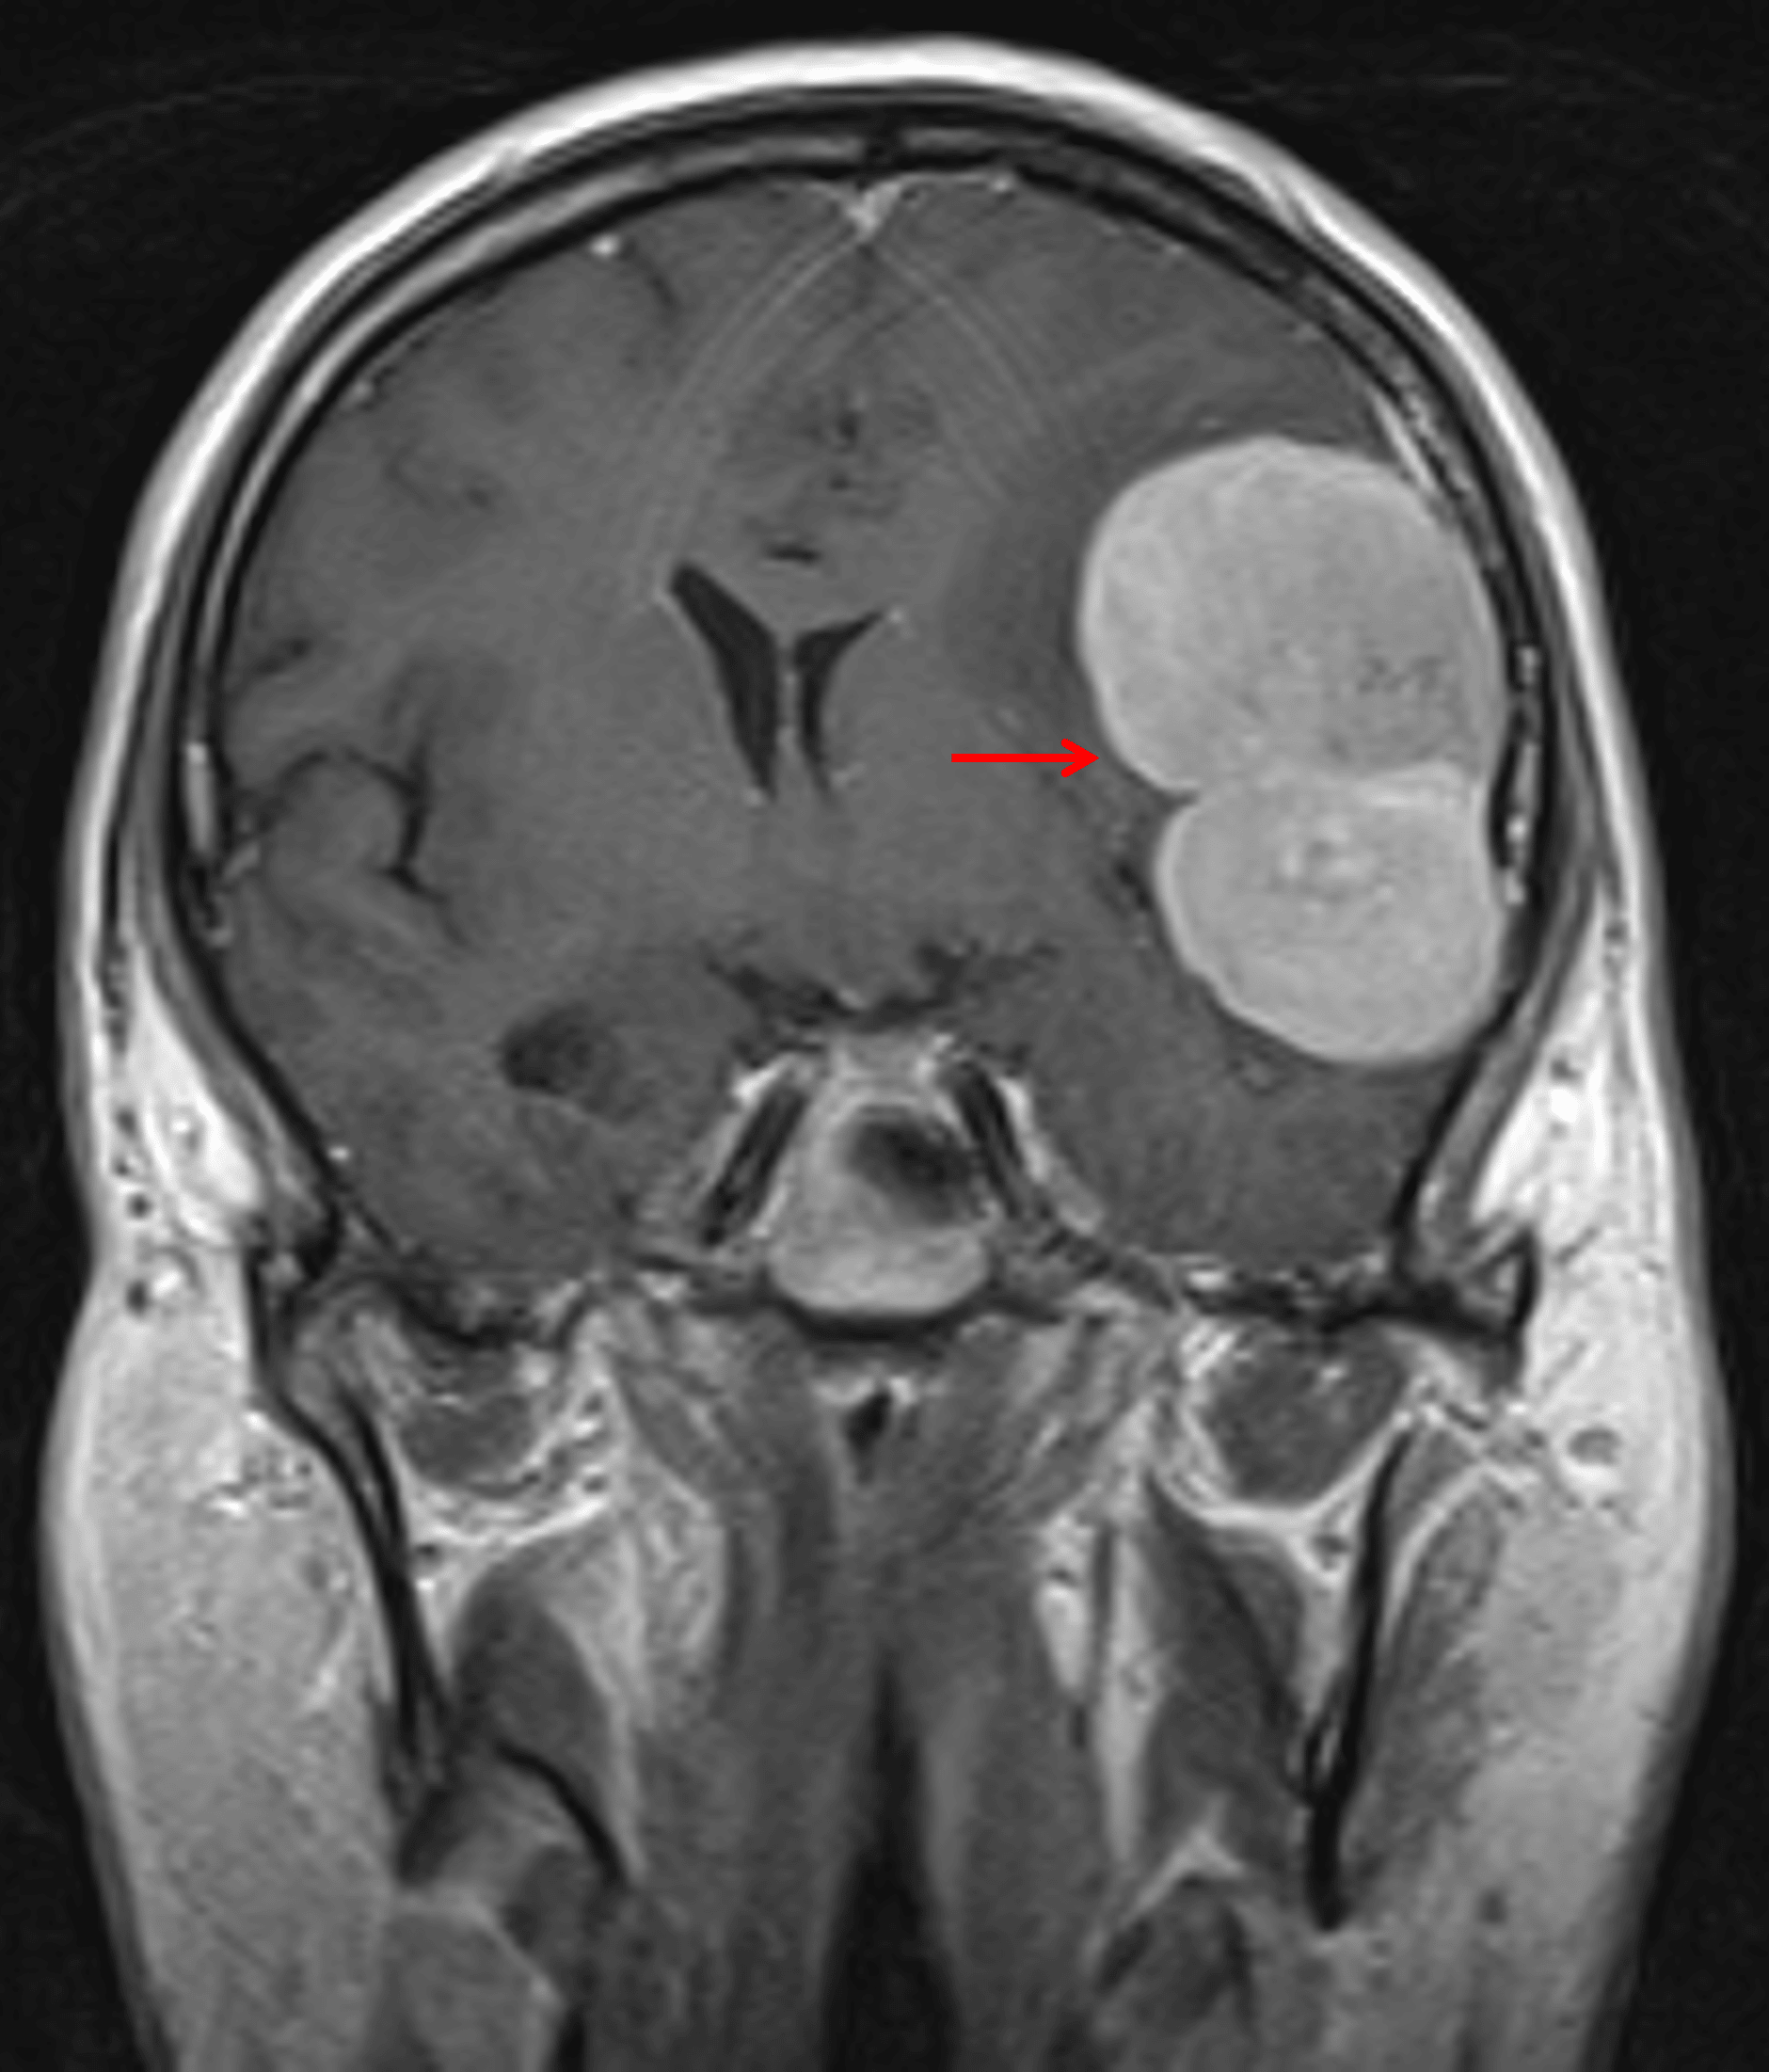

MRI

- T1 isointense, mildly T2 hyperintense, diffusely enhancing extra-axial mass overlying the left sylvian fissure measuring 6 x 4.2 x 6.4 cm

- Small internal areas of more pronounced T2 signal hyperintensity

- Mild corresponding restricted diffusion throughout the mass

- Surrounding vasogenic edema

- Associated mass effect resulting in local sulcal effacement, crowding of the left lateral ventricle, 7 mm left-to-right midline shift, and medialization of the left temporal uncus with crowding of the basal cisterns and mass effect on the midbrain

Avidly enhancing mass with lobulated contours (red arrow).